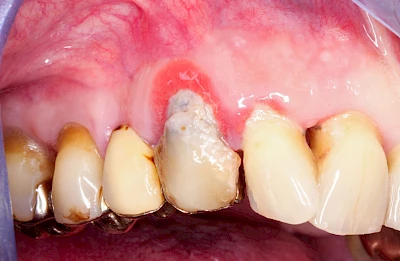

Bei einer Fistel hat sich meist eine Entzündung (manchmal auch Erreger selbst) z. B. aufgrund von Karies oder aufgrund eines Unfalls über den Zahnnerv und die Wurzelspitze (Apex) in den umliegenden Knochen ausgebreitet (apikale Parodontitis) und schnell einen Weg durch den umgebenden Knochen und die aufliegende Schleimhaut in die Mundhöhle gebahnt.

Fisteln sind in der Regel nicht schmerzhaft und fallen häufig als kleine Öffnung weiter entfernt vom Zahnfleisch nahe der Umschlagfalte auf. Aus der Fistelöffnung entleert sich spontan gelbliches Sekret (Eiter) oder es lässt sich mit dem Finger ausstreichen. Manchmal beschreiben die betroffenen Menschen immer wieder einen komischen Geschmack im Mund.

Im fortgeschrittenen Stadium kann die Schleimhaut sich weiter zurückgezogen haben und die Wurzelspitze sichtbar sein. In der Regel treten bei Fisteln keine Schwellungen auf, weil sich die Entzündung nicht im Gewebe ausbreitet.